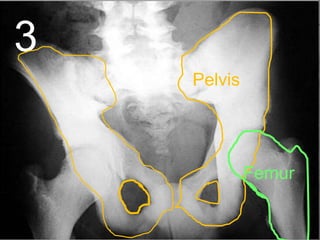

• Your pelvis helps protect the bladder,

intestines, and reproductive organs in

women.

Pelvis

3

Femur